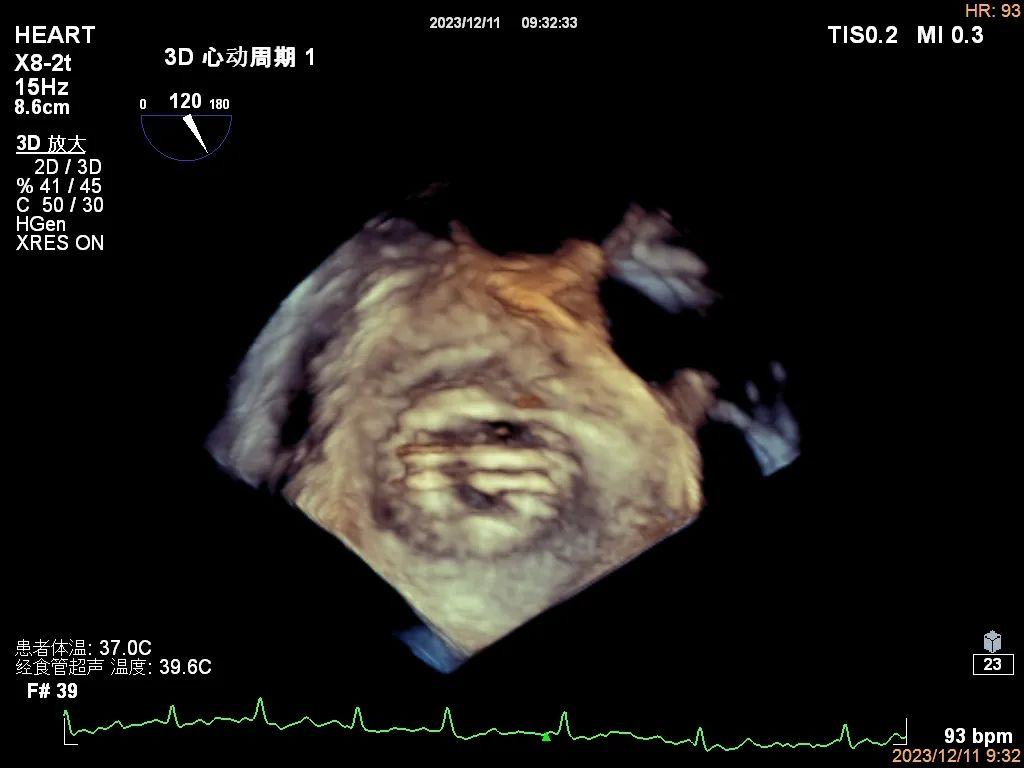

2、人工瓣膜功能的评价:更直观显示人工瓣瓣叶结构(人工瓣有无血栓、血管翳、卡瓣等),人工瓣与周围结构组织关系(有无瓣周漏等)。

人工二尖瓣机械瓣三维图